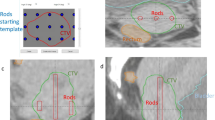

Following the IC + IS-BT application, a whole pelvis computed tomography scan (Aquilion™ Large Bore, 3-mm slice thickness), and a pelvic magnetic resonance imaging (MRI) simulation were performed as recommended by the GEC-ESTRO Working Group [18]. The GTV-T, HR-CTV, and OAR (bladder, rectum, sigmoid, and bowel bag) were contoured on the MRI, using the EMBRACE II protocol guidelines [6]. Volumes contoured on the MRI were transferred to the CT with co-registration performed by matching the applicator on the CT with the applicator on the MRI. The use of a Foley catheter with a clamp allowed for consistent bladder filling (100 cc) in patients with an empty rectum, reducing spatial variability. As no planning target volume (PTV) nor planning (organ at) risk volume (PRV) margins were used for any structure, all structures were identical for each boost modality.

All patients were treated with the microSelectron® Digital HDR (high dose rate). The Varian Medical System (Eclipse) was used to create a 3D IC + IS-BT plan. Dose-volume adaptation began with the activation of the uterine applicator and ovoid source positions, follow by a point normalization, then a manual dwell location and time optimization in the needles channels. All the treatment procedures described in this study were part of our department’s standard clinical practice. The equivalent doses in 2 Gy fractions (EQD2) of EBRT and BT for CTV-HR and OAR were calculated using the linear-quadratic model with α/β of 10 (EQD210) and 3 (EQD23), respectively. The EMBRACE II protocol was used during plan optimization [6].

For every IC + IS-BT treatment plan, one IC-BT plan and one SBRT plan were created. The plans were created using the same contouring volumes (target and OAR) as the IC + IS-BT plan and were calculated using the same CT scan. The uterine applicator and needle channels were converted to water density for the SBRT plans.

When normalizing to the target, the mean EQD23_D2cc of OARs was significantly higher with IC-BT (Table 2). In particular, bladder EQD23 D2cc hard constraints (< 90 Gy) were not achieved when boosting with IC-BT (Fig. 1). Adding IS needles to IC BT results in a median absolute reduction of bladder EQD23 D2cc of 1 Gy (i.e. a relative dose reduction of 19%), thereby achieving the hard dose constraint (Fig. 1; Table 2). SBRT without PTV (vs. IC-BT and vs. IC + IS-BT) provides significantly lower OARs EQD23_D2cc dose to the bladder; bowel and rectum (Table 2). For the sigmoid constraints, there was no significant difference (p = .08) between the three boost modalities (Table 2).

When normalizing to the OARs while escalating the dose to the target, IC-BT provides a significantly lower mean dose to the EQD210 D90% of HR-CTV (6.62 Gy (6.24-7)) and cannot achieve the coverage goal of 7.1 Gy (Fig. 2; Table 2). SBRT without PTV delivers the highest dose to the D90% HR-CTV (9.02 Gy), but significantly lower doses to the D50% (9.83 Gy) and D30% (10.1 Gy) (Table 2). Between the IC-BT and IC-BT + IS modalities, the D30 HR CTV did not significantly change (p = .37) (Table 2).